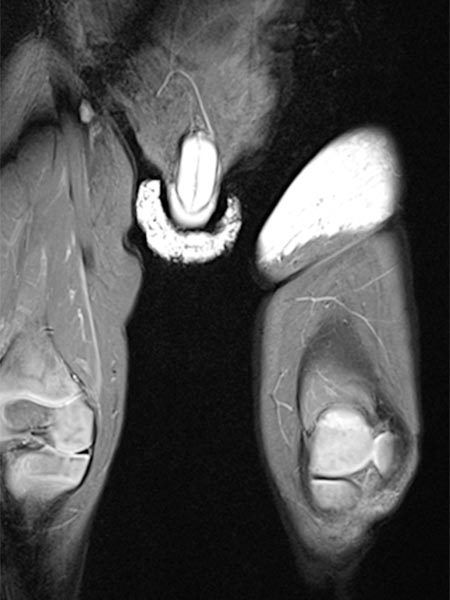

Axial, T2-weighted, fat-suppressed MRI of the patient at 7 years and 10 months of age.

The NICH is still visible under the skin as a hyperintense (white) flat structure, but significantly smaller than before embolization.